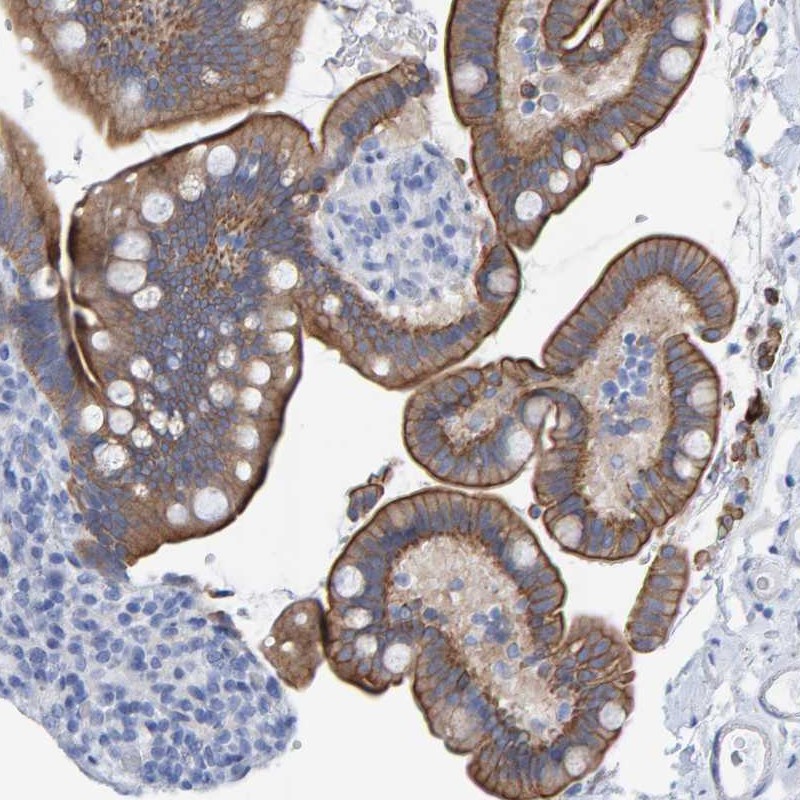

Immunohistochemical staining of human colon shows moderate cytoplasmic and membranous positivity in glandular cells.